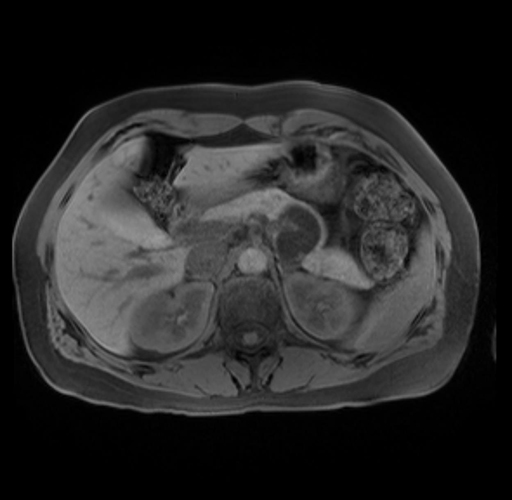

Imaging Analysis

Look through the patient's CT scan to identify any areas of concern for the necessary procedure.

Based on your CT findings, which issue(s) are present and would give reason for "planned slowing down moment(s)" in this case?